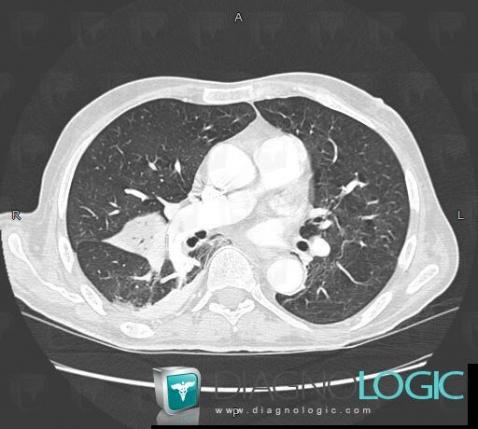

Pulmonary thromboembolism, Pulmonary artery, CT

Here is the specific information in the key image above:

- Diagnosis Pulmonary thromboembolism, Location(s) Pulmonary artery, with gamuts thoracic vascular disease